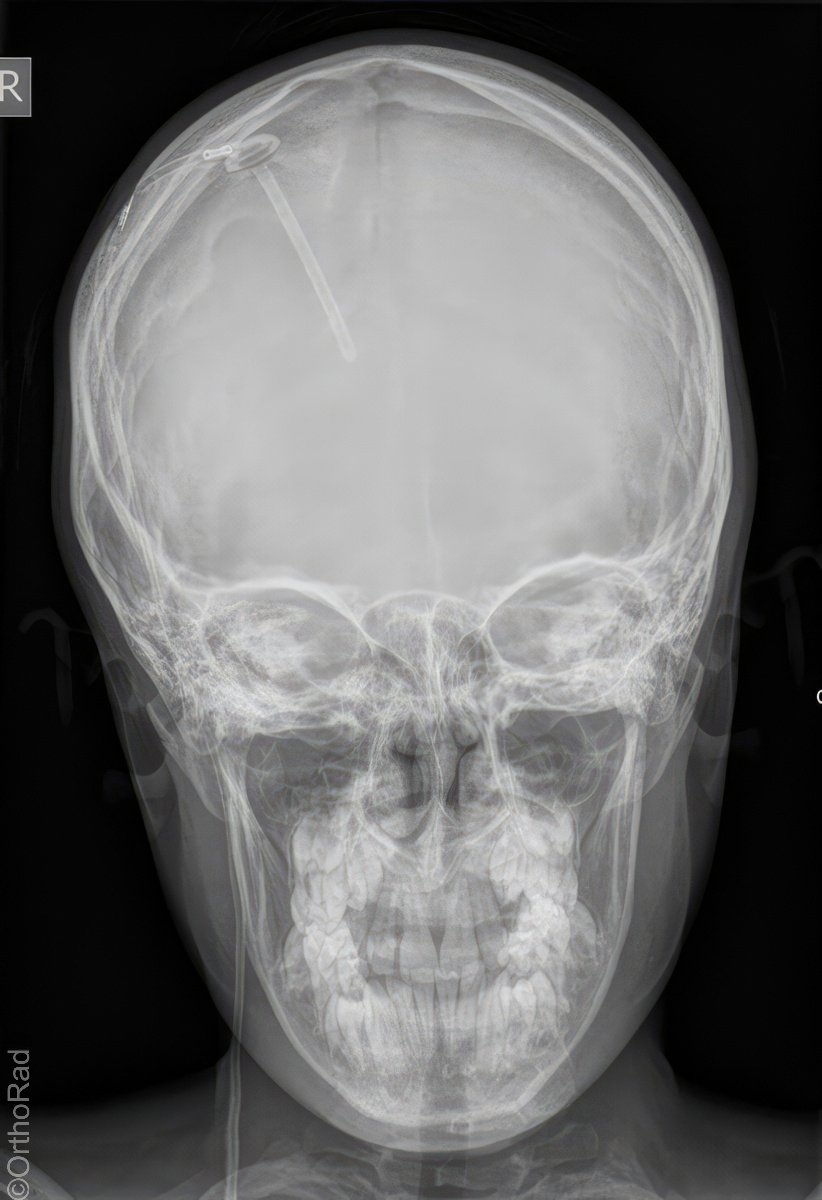

Schädel a.-p.

Technik

• FDA: 1,15 m

• Ausgangsformat: 24/30

• mit Raster

Indikation

Fremdkörper-Lokalisation vor MRT, Shuntkontrolle

Lagerung

Rückenlage

Schädel liegt exakt gerade

Kinn anziehen bis Deutsche Horizontale senkrecht zur Bildebene

(ggf. 15° Keil unter den Kopf)

Zentralstrahl

Querstrahl: ca. Nasenwurzel

Längsstrahl: Medianebene

Einblendung

Haaransatz & Hautgrenze

Qualitätskriterien

Symmetrische Abbildung beider Schädelhälften, Nasenscheidewand streng in der Mitte. Die Felsenbeine stellen sich im unteren bis mittleren Drittel der Orbita da. Felsbeinspitzen projizieren sich in die Mitte der Orbita oder eher etwas oberhalb davon.